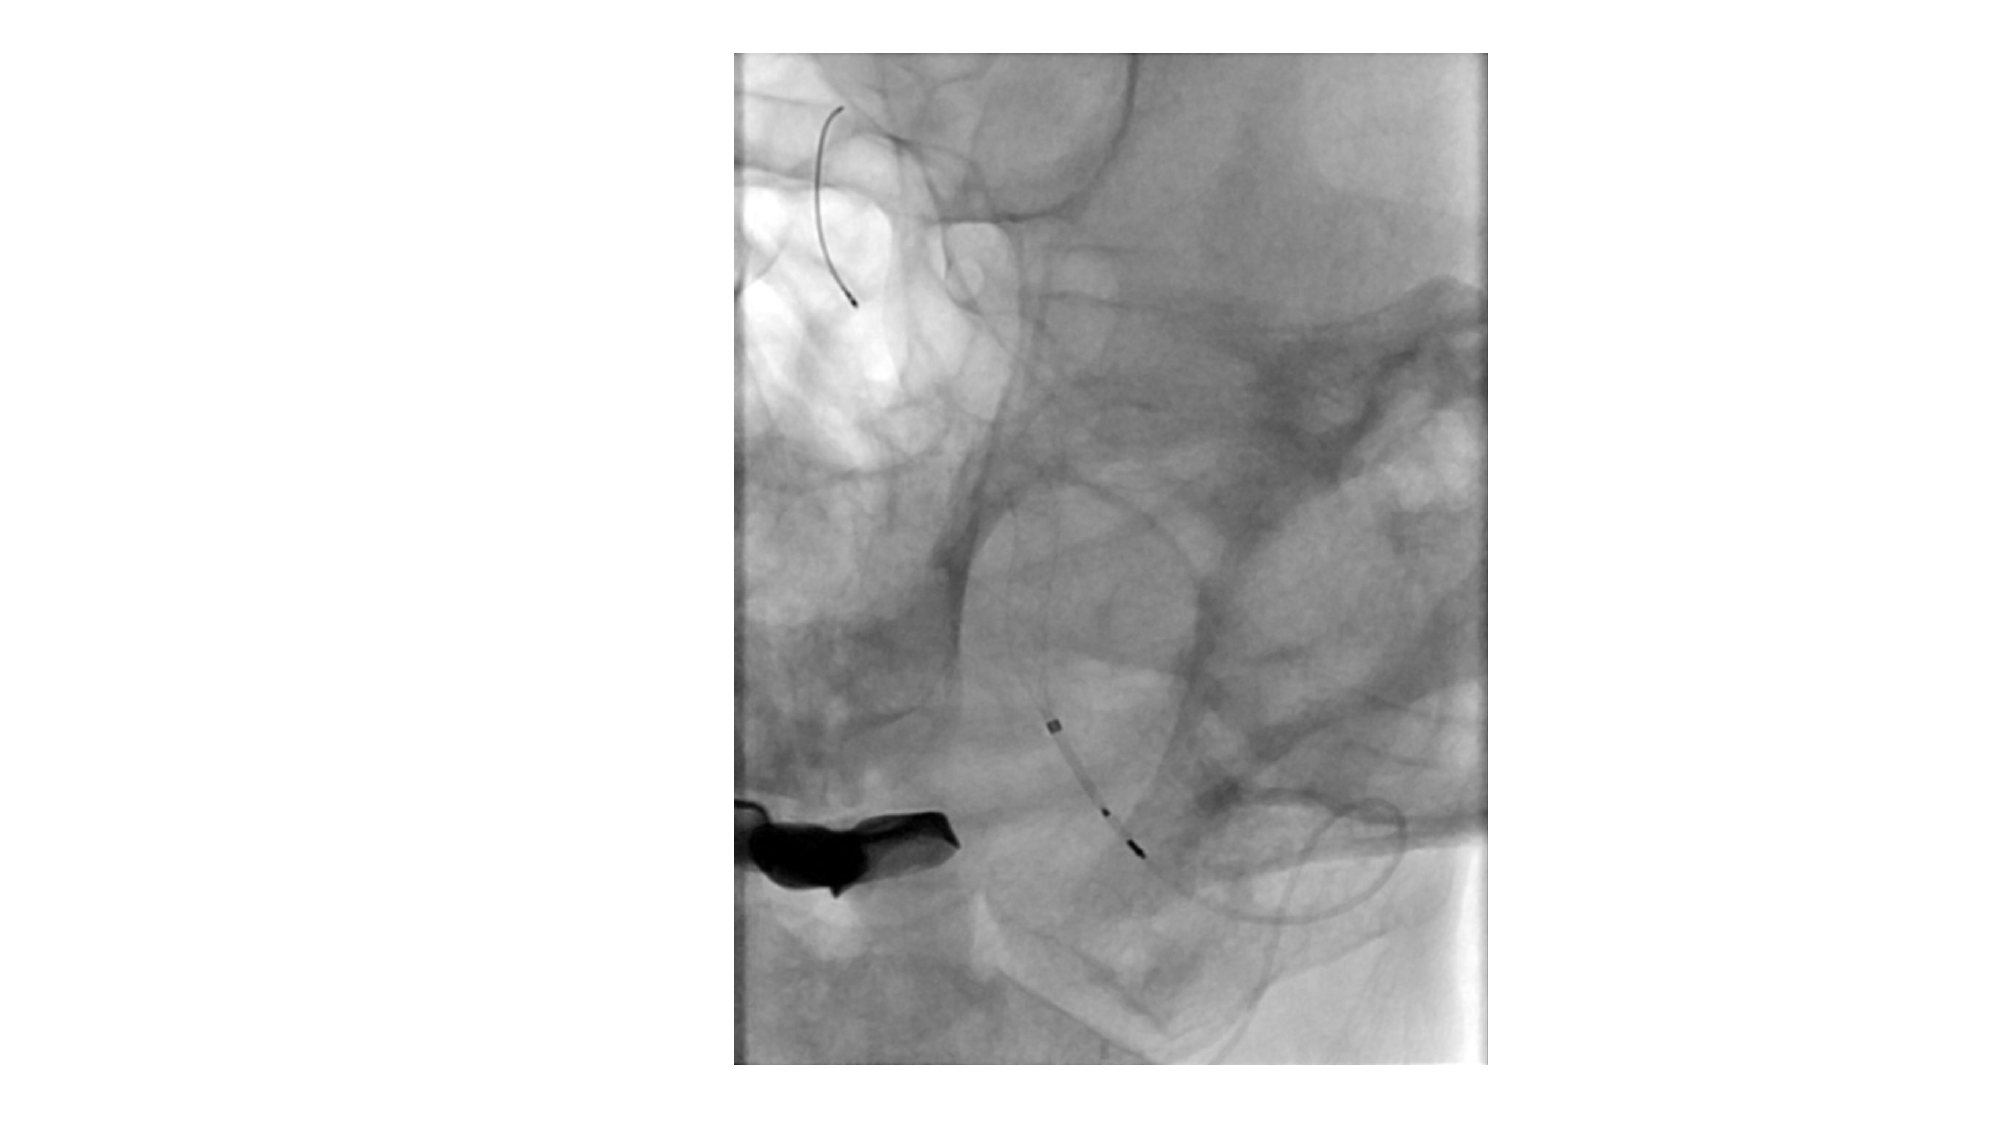

| 13:30 - 14:10 | Surgical management of skull base trauma Endovascular Management of Post-Traumatic Intracranial Vascular Lesions | Assoc. Prof. Nguyen Trong Yen Dr. Nguyen Ngoc Cuong | |

| 15:10 - 16:10 | Interactive Case Demonstration and Discussion II: ~20 minutes each, (5 minutes presentation followed by 15 minutes discussion) Practicals: How I am doing it? Participants present case presentations about how they do it? The faculty comment on and discussion. 1. Endoscopic approach in post-traumatic CSF leakage - Dr. Nguyen Thanh Xuan 2. Endovascular approach in CCF - Assoc. Prof. Le Thanh Dung | Prof. Christian Matula International & local faculties Participants | |